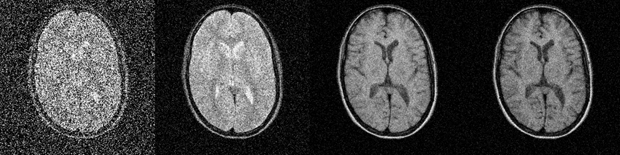

For many MR imaging data acquisitions, two data averages suffice for the cre­a­tion of images with good SNR. For n data-averaging runs, the net increase of S/N will be the square root of n. The S/N will, for example, increase by a factor of 2 if four data averages (numbers of excitations) are performed (Figure 09-07 and Figure 09-08).

Figure 09-07:

a 2; b 8; c 32; and d 128 data ave­ra­ges. The ‘polluting noise’ disappears slow­ly with higher num­ber of averages.